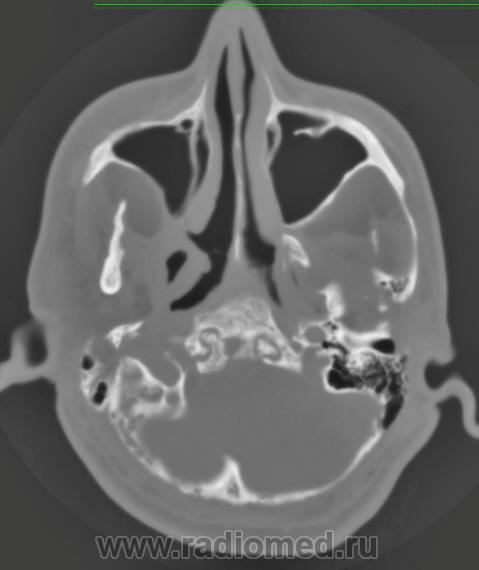

Nela. КТ головного мозга и костей. Гистиоцитоз Х (морфологическая верификация).

Пациент - молодой человек, предъявляет жалобы на головные боли и боли в шее. Болеет с 2002 года.

Гистиоцитоз Х – заболевание ретикулоцитарной системы неизвестной этиологии, морфологически характеризующееся первичной пролиферацией своеобразных гистиоцитов (клеток Лангерганса или клеток Х) и образованием в легких и в других органах и тканях гистиоцитарных гранулем и гранулематозных инфильтратов.

Заболевание относится к системным: гранулемы могут образовываться в различных органах, но наиболее часто поражаются легкие и кости. Заболевают чаще всего люди молодого возраста, между 20 и 40 годами, большей частьюмужчины.

Такое обширное поражение нечасто встречается. Я вижу впервые.

Конечно чаще, но не каждый день. Гистиоцитоз Х или эозинофильная гранулема, или гистиоцитоз из клеток Лангерганса редкое заболевание. Но, думаю, каждый рентгенолог со стажем видел костный гистиоцитоз в костях свода или в позвонке. У нас областное гематологическое отделение, поэтому наверно раз в 1-2 года встречаем.